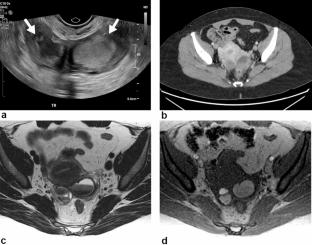

子宫内膜异位症是一种常见的妇科疾病,具有显著的发病率负担,通常需要大量的诊断延迟。虽然经阴道超声(TVUS)是慢性盆腔疼痛和不孕症等症状的一线成像工具,但它在检测深部子宫内膜异位症方面存在局限性。2024年,超声放射科医师协会(SRU)发布了建议,通过将额外的技术纳入标准tvu来增强检测。本文概述了在社区实践中以最小的额外扫描时间提高诊断准确性的实际适应性。它涵盖了患者选择、利益相关者参与、培训和质量保证,同时解决了实施方面的挑战。社区超声实践在早期发现、指导患者接受适当治疗方面发挥着关键作用。

Endometriosis is a common gynecologic disorder with a significant burden of morbidity that is often subject to substantial diagnostic delay. While transvaginal ultrasound (TVUS) is the first-line imaging tool for symptoms like chronic pelvic pain and infertility, it has limitations in detecting deep endometriosis. In 2024, the Society of Radiologists in Ultrasound (SRU) issued recommendations to enhance detection by incorporating additional techniques into standard TVUS. This article outlines practical adaptations to improve diagnostic accuracy with minimal extra scan time in community practices. It covers patient selection, stakeholder involvement, training, and quality assurance while addressing implementation challenges. Community ultrasound practices play a key role in early detection, guiding patients toward appropriate care.

Graphical abstract